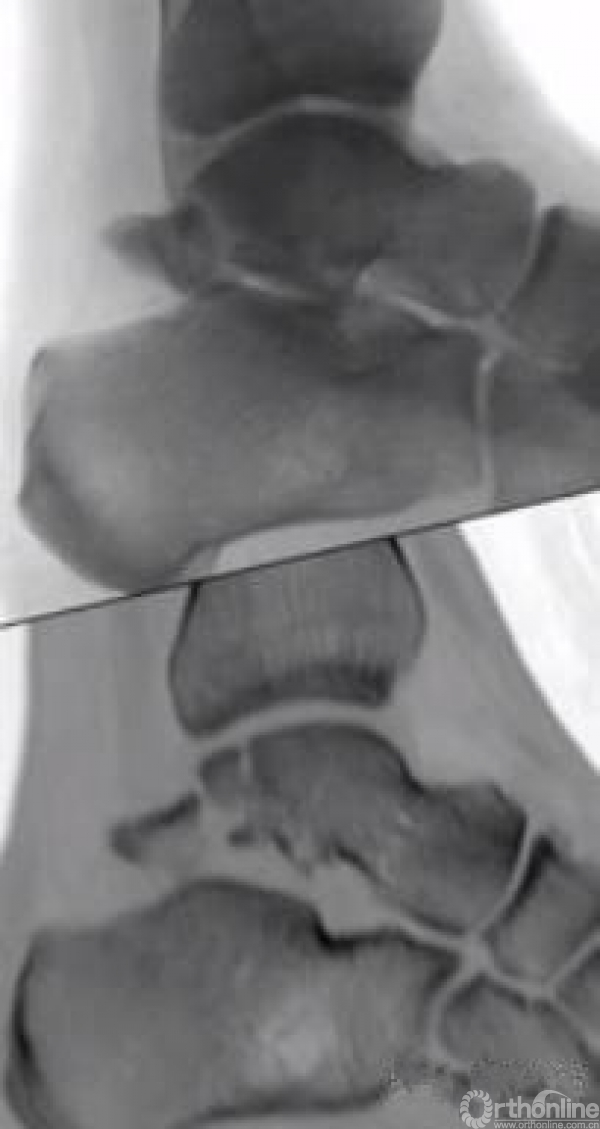

当发生骨折脱位时,由于位移巨大,导致相应位移的血管损伤、最终导致距骨坏死,所以距骨骨折的分型常用Hawkins分型,距骨坏死率随分型严重程度逐渐增加。

移位的体部骨折和II-IV型(2mm以上)的颈部骨折移位